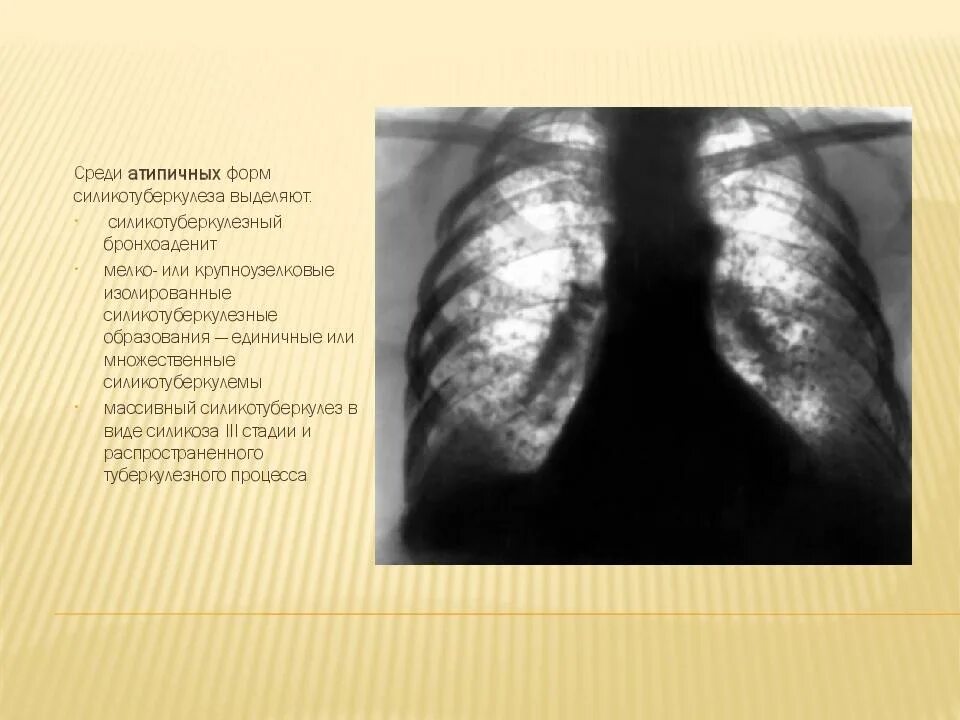

Бронхоаденит это